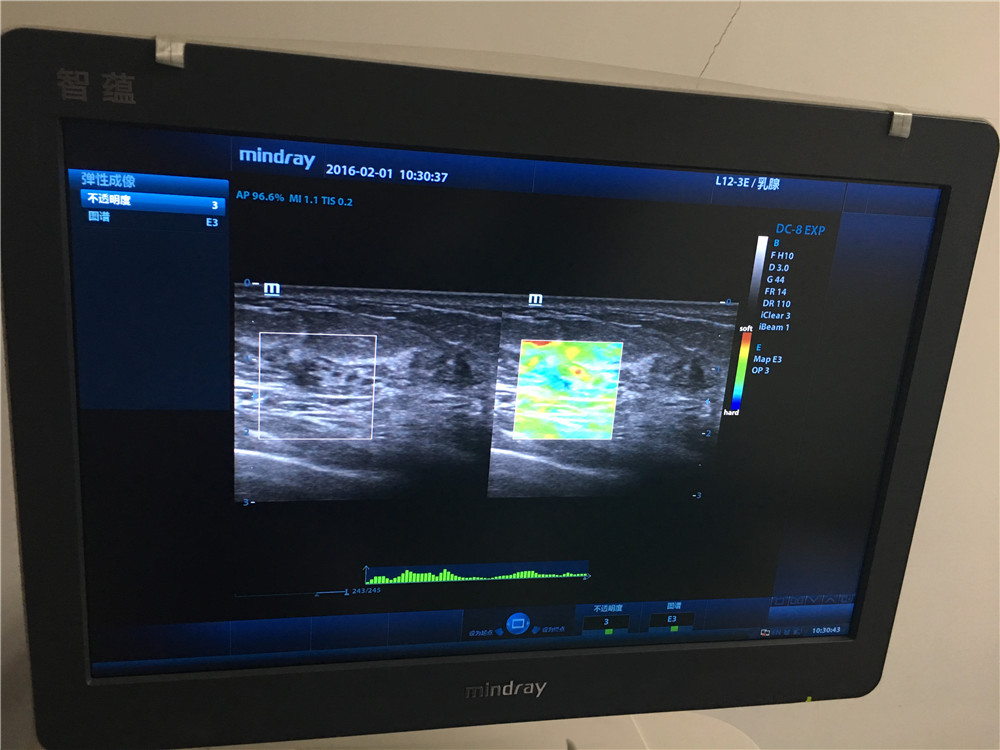

功能科开展超声弹性成像新技术

为进一步提高乳腺检查的敏感性和诊断的准确性,我院功能科在全市率先引进弹性成像这一辅助新技术,为早期诊断、鉴别乳腺肿瘤的良、恶性及早期治疗提供的一种新的有效途径。 作为一种全新的成像技术,弹性成像扩展了超声诊断理论的内涵和超声诊断范围,弥补了常规超声的不足,能更生动的显示、定位病变及鉴别病变性质,使现代超声技术更为完善。实时组织弹性成像不仅能帮助早期发现不易触及的微小及深在的病灶,在识别传统灰阶声像图上难以发现的病变浸润区域上也有优势,还能鉴别一些临床上较难诊断的乳腺病灶,如不典型的乳腺病及炎性病变。并且,如果弹性成像图与灰阶声像图上肿瘤的大小比较确可作为一种可靠的检测指标,那么临床早期发现恶性乳腺癌的比率将大大提高,需要接受活检以确定良恶性的患者数也将大大减少,既可帮助减轻社会医疗保健的经济负担,也可减轻患者自身身体和心理上的痛苦。其在临床上的应用包括:1.癌症的早期诊断;2.病变的良性、恶性判断;3.癌变扩散区域的确定;4.治疗效果的确认。

组织弹性成像除了在乳腺疾病方面研究较为深入,技术成熟外,目前还应用于前列腺、甲状腺等小器官,可有效鉴别实质性肿瘤的良恶性,对于恶性病变诊断具有较高的特异性和敏感性。另外还应用于肝纤维化的诊断、局部心肌功能评价以及高强度聚焦超声与射频消融引起的损害的检测与评估。